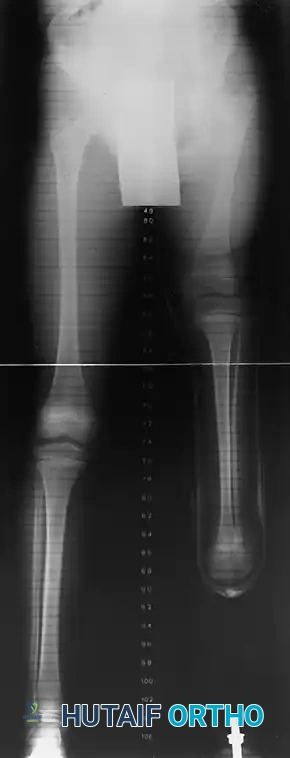

- Type 1A Deformity: There is complete radiographic absence of the tibia and a hypoplastic distal femoral epiphysis compared with the contralateral normal side.

- Type 1B Deformity: There is no radiographic evidence of an ossified tibia; however, the distal femoral epiphysis appears more normal in size and shape. This distinction is critical because Type 1B deformities possess a proximal tibial cartilaginous anlage that can be expected to ossify over time. Modern imaging techniques, such as high-resolution ultrasound and MRI, are mandatory to identify this cartilaginous anlage.

- Type 2 Deformity: A proximal tibia of varying size is present and ossified at birth. The fibula is usually normal in size, but the fibular head is proximally dislocated.

- Type 3 Deformity: The proximal tibia is not radiographically visible, but the distal tibial epiphysis is present. This is an exceptionally rare variant. The distal femoral epiphysis is usually well-formed, but the upper end of the fibula is proximally dislocated, leading to profound knee instability.

- Type 4 Deformity: The tibia is shortened, and there is proximal migration of the fibula with distal tibiofibular diastasis. This rare deformity is also referred to as congenital diastasis of the ankle joint. The distal tibial epiphysis may be entirely absent.

As with all congenital lower limb deficiencies, the ultimate goal of treatment is to provide a functional, stable limb that is equal in length to the normal limb, allowing for energy-efficient ambulation. The specific surgical intervention depends heavily on the radiographic classification, the presence of a cartilaginous anlage, and the clinical integrity of the extensor mechanism.